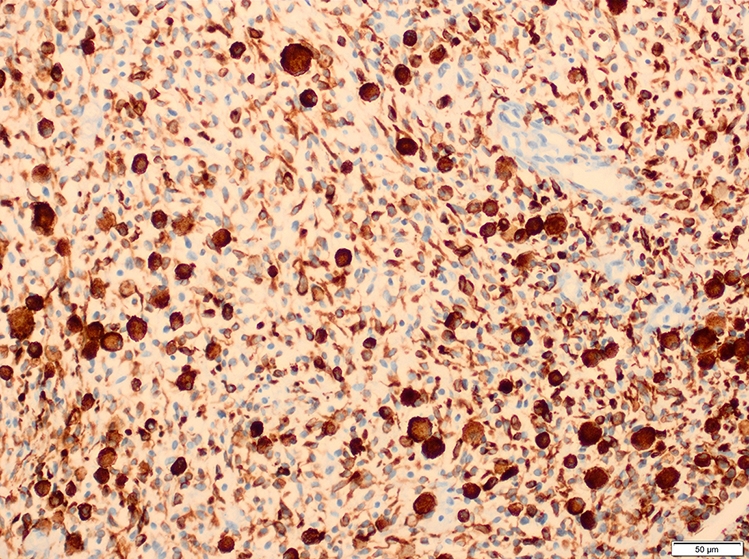

Positive stains

- Desmin, MyoD1 or myogenin are critical to document (Pathol Oncol Res 2008;14:233)

- Without myogenic differentiation (MyoD1 or myogenin), it is very difficult to diagnose embryonal rhabdomyosarcoma

- These stains will be less diffuse than in alveolar rhabdomyosarcoma and can be extremely focal

- Vimentin in all cells (even most primitive)

- Actin, myoglobin, myosin and creatine kinase M staining in more differentiated cells

- There may be aberrant staining for several antigens: occasional immunoreactivity to cytokeratin, S100 protein, neurofilaments and B cell markers such as CD20

- PAS highlights glycogen in most tumors

- Botryoid variant: Desmin, MyoD1, smooth muscle actin, muscle specific actin (Pediatr Dev Pathol 2005;8:427)